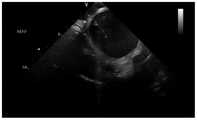

图3是示例超声扇面下的上腔静脉、右心房结构;Figure 3 is an example of the superior vena cava, right atrium structure below the ultrasound fan;

通过超声导管的手柄操作打出上腔静脉扇面,具体的操作步骤为:首先旋转手柄上的锁住按钮;然后顺时针旋转手柄,当扇面中出现左侧肺静脉扇面时旋转手柄上的P弯直至出现一半的主动脉扇面时停止旋转P弯;最后旋转手柄上的R弯直至上腔静脉扇面出现。(见图3)The superior vena cava fan is created through the handle operation of the ultrasonic catheter. The specific operation steps are: firstly rotate the lock button on the handle; then rotate the handle clockwise, when the left pulmonary vein fan appears in the fan, rotate the P curve on the handle until it appears Stop rotating the P-curve halfway through the aortic fan; finally rotate the R-curve on the handle until the superior vena cava fan appears. (see Figure 3)